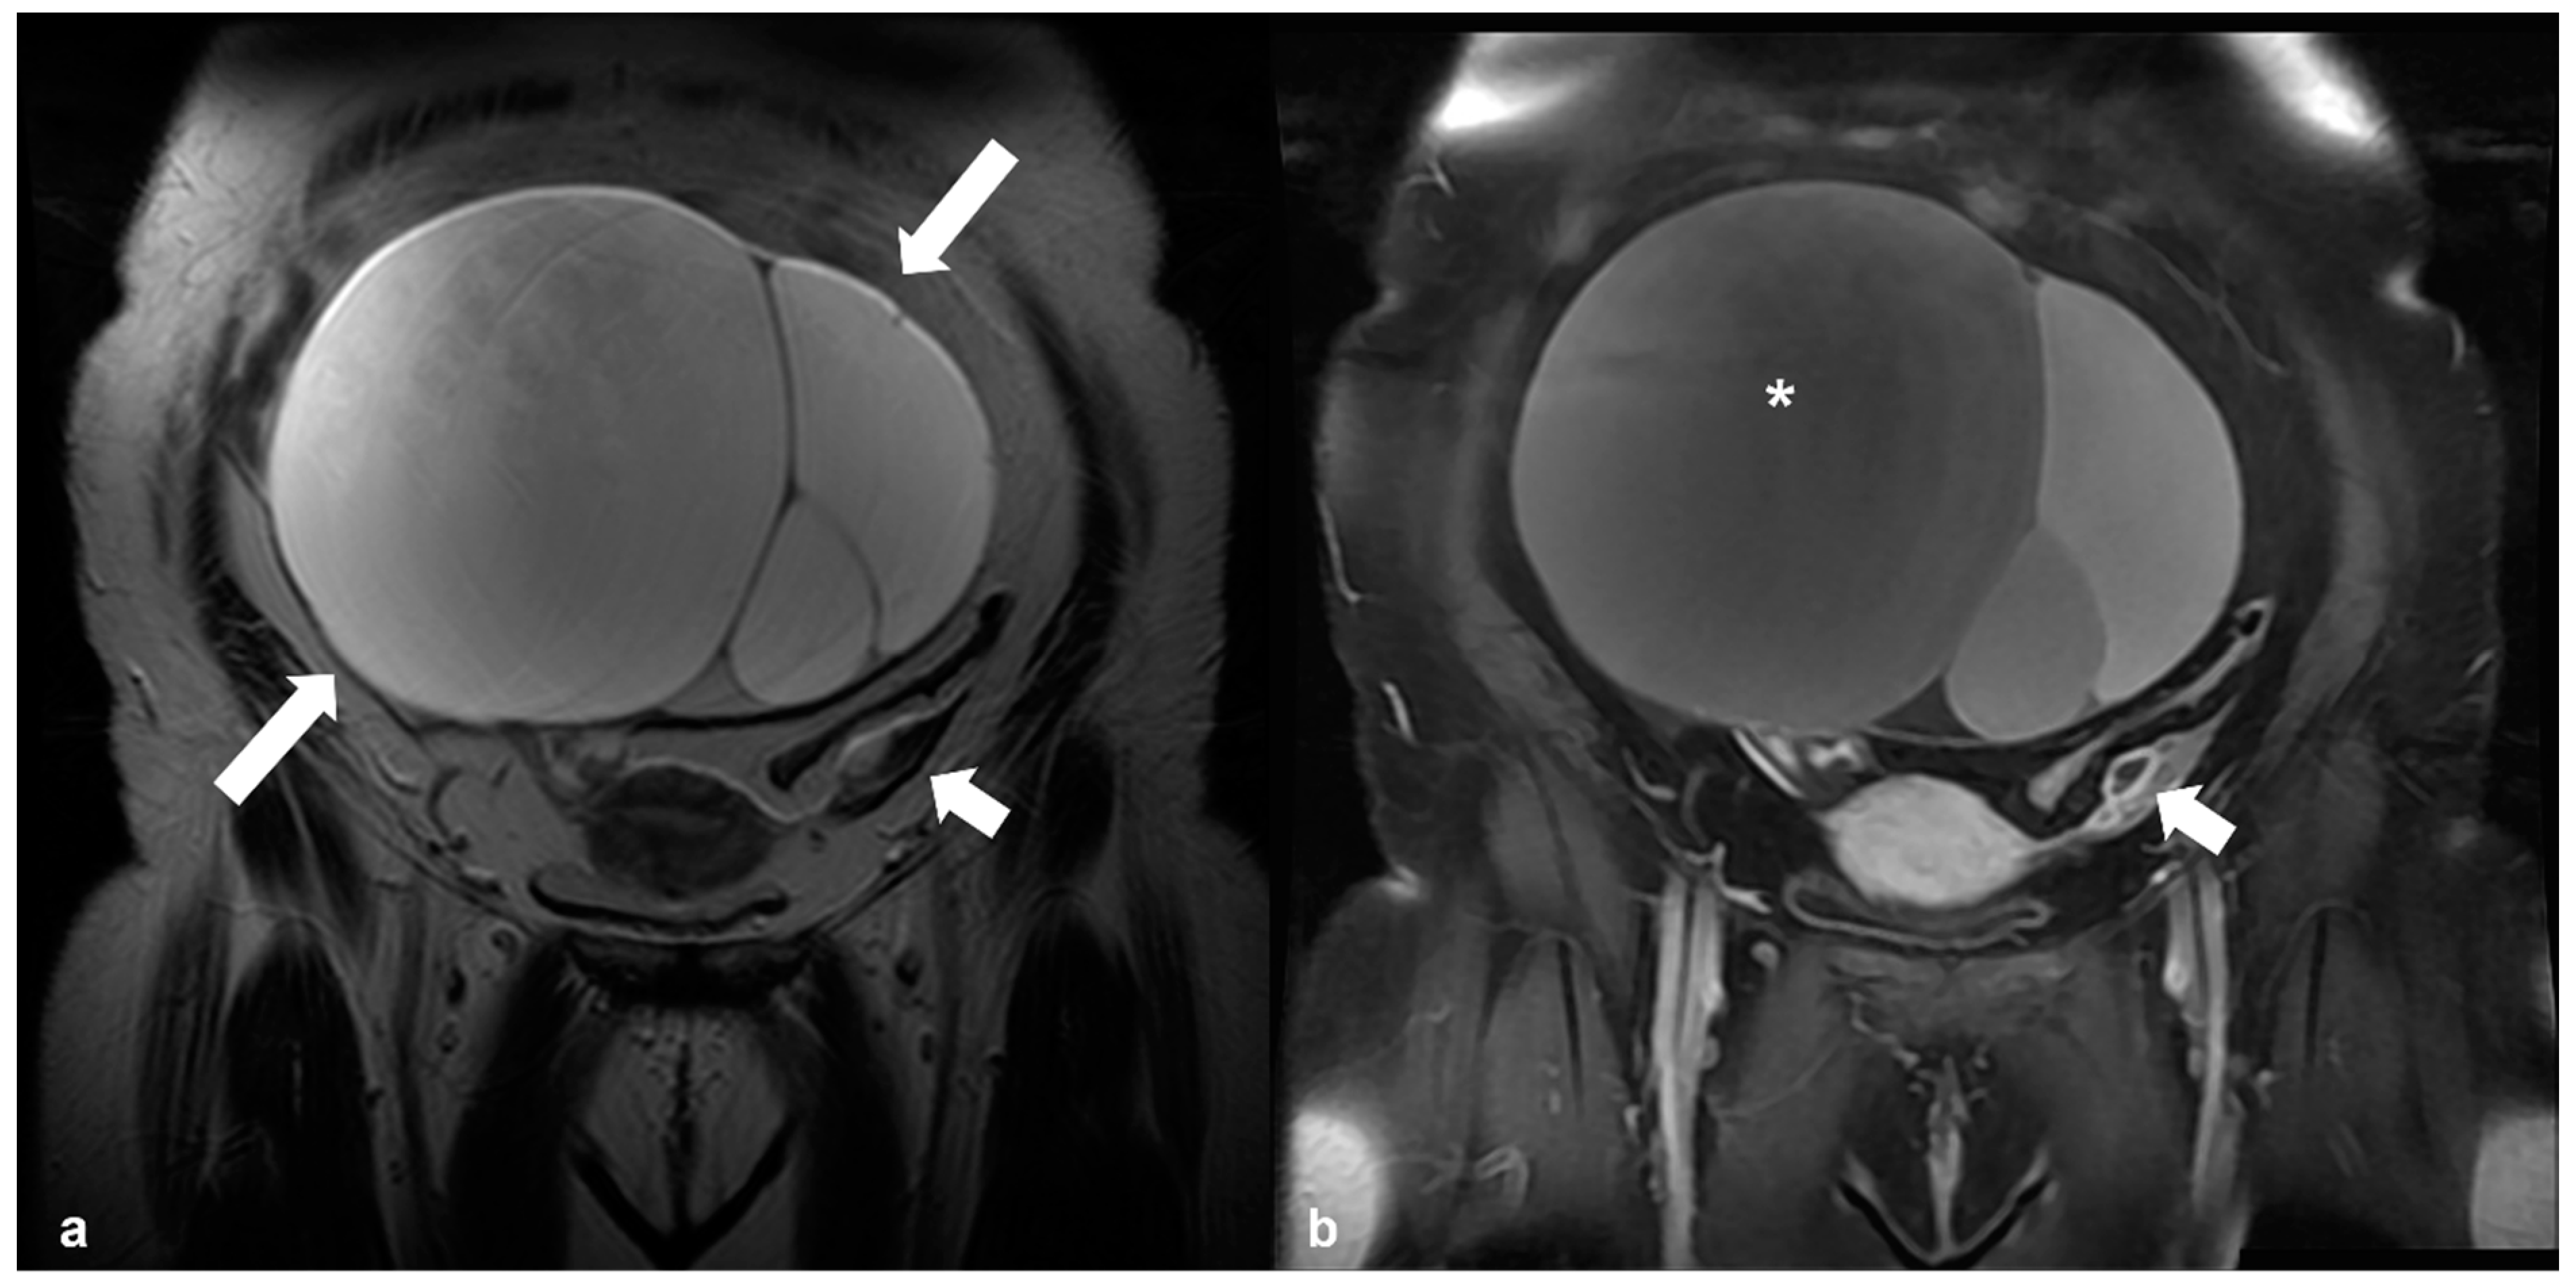

2.4.3. Dysgerminoma

2.5. Pregnancy